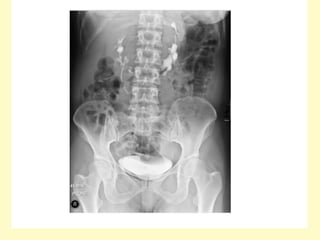

Intravenous urogram showing right-sided hydronephrosis and the

dilation of the proximal ureter up to the level of the L3 transverse

process, the medial deviation of the ureter at this level (arrow) gives

rise to the typical fish hook or reversed S appearance